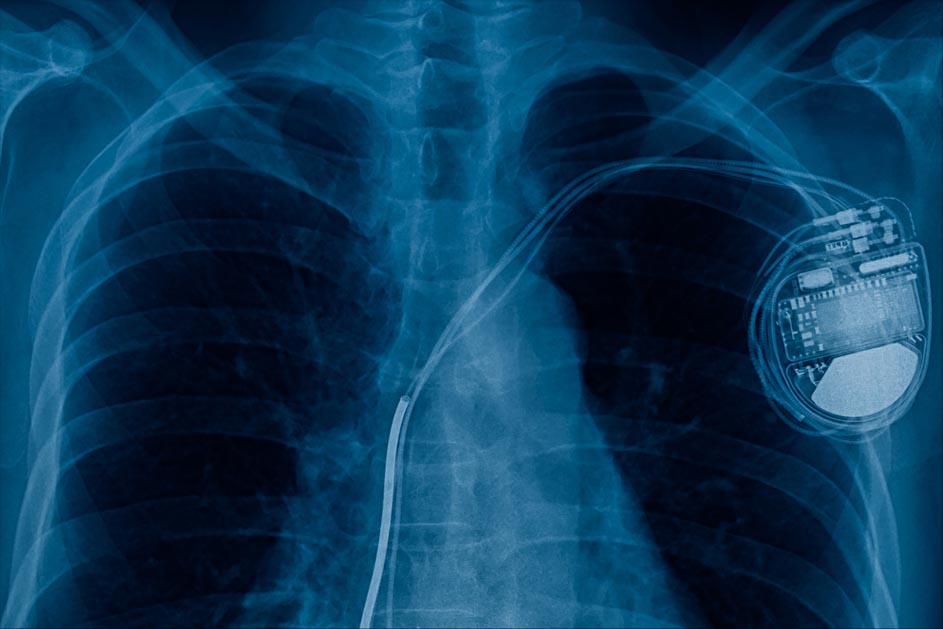

Cardiac implantable electronic devices (CIEDs), such as pacemakers and implantable defibrillators, save and extend lives. They are amazingly reliable and effective, but even the best tool comes with risks. As many as 1 in 20 patients with a CIED develops an infection within three years of implantation.